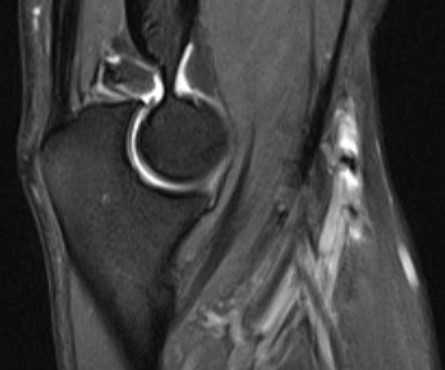

Серия Т1-взвешенных томограмм правого локтевого сустава во фронтальной проекции с направлением срезов от заднего отдела к переднему. Сухожилие трехглавой мышцы прикрепляется к локтевому отростку. Начинают хорошо визуализироваться локтевая мышца и глубокий сгибатель пальцев. На срезе появляются сухожилия локтевого сгибателя запястья и локтевого разгибателя запястья. Серия Т1-взвешенных томограмм левого локтевого сустава во фронтальной проекции с направлением срезов от заднего отдела к переднему. Сухожилие трехглавой мышцы прикрепляется к локтевому отростку. Начинают хорошо визуализироваться локтевая мышца и глубокий сгибатель пальцев. На срезе появляются сухожилия локтевого сгибателя запястья и локтевого разгибателя запястья. Позади медиального надмыщелка можно увидеть локтевой нерв. Латеральная локтевая коллатеральная связка формирует петлю позади шейки лучевой кости, обеспечивая заднелатеральную стабилизацию. Общее сухожилие разгибателей длинное и тонкое, тогда как общее сухожилие сгибателей — короткое и широкое. Позади медиального надмыщелка можно увидеть локтевой нерв. Латеральная локтевая коллатеральная связка формирует петлю позади шейки лучевой кости, обеспечивая заднелатеральную стабилизацию. Общее сухожилие разгибателей длинное и тонкое, тогда как общее сухожилие сгибателей — короткое и широкое. Лучевой нерв проходит между плечевой и плечелучевой мышцами. Дистальный отдел сухожилия двуглавой мышцы приближается к месту своего прикрепления к бугристости лучевой кости. Хорошо видны контуры бугристости лучевой кости. Плечевая мышца покрывает переднюю поверхность тела плечевой кости. Лучевой нерв проходит между плечевой и плечелучевой мышцами. Дистальный отдел сухожилия двуглавой мышцы приближается к месту своего прикрепления к бугристости лучевой кости. Хорошо видны контуры бугристости лучевой кости. Плечевая мышца покрывает переднюю поверхность тела плечевой кости. Круглый пронатор огибает переднюю поверхность предплечья. Сухожилия плечевой и двуглавой мышц визуализируются на пути к местам прикреплений. Лучевой нерв разделился на поверхностную и глубокую ветви. Срединный нерв проходит латеральнее круглого пронатора. Круглый пронатор огибает переднюю поверхность предплечья. Сухожилия плечевой и двуглавой мышц визуализируются на пути к местам прикреплений. Лучевой нерв разделился на поверхностную и глубокую ветви. Срединный нерв проходит латеральнее круглого пронатора. Из мышц предплечья все еще визуализируется только плечевая мышца. Все еще визуализируется двуглавая мышца плеча. Непосредственно ниже подкожной жировой клетчатки все еще прослеживаются двуглавая мышца плеча и латеральная подкожная вена руки. Из мышц предплечья все еще визуализируется только плечевая мышца. Все еще визуализируется двуглавая мышца плеча. Непосредственно ниже подкожной жировой клетчатки все еще прослеживаются двуглавая мышца плеча и латеральная подкожная вена руки.